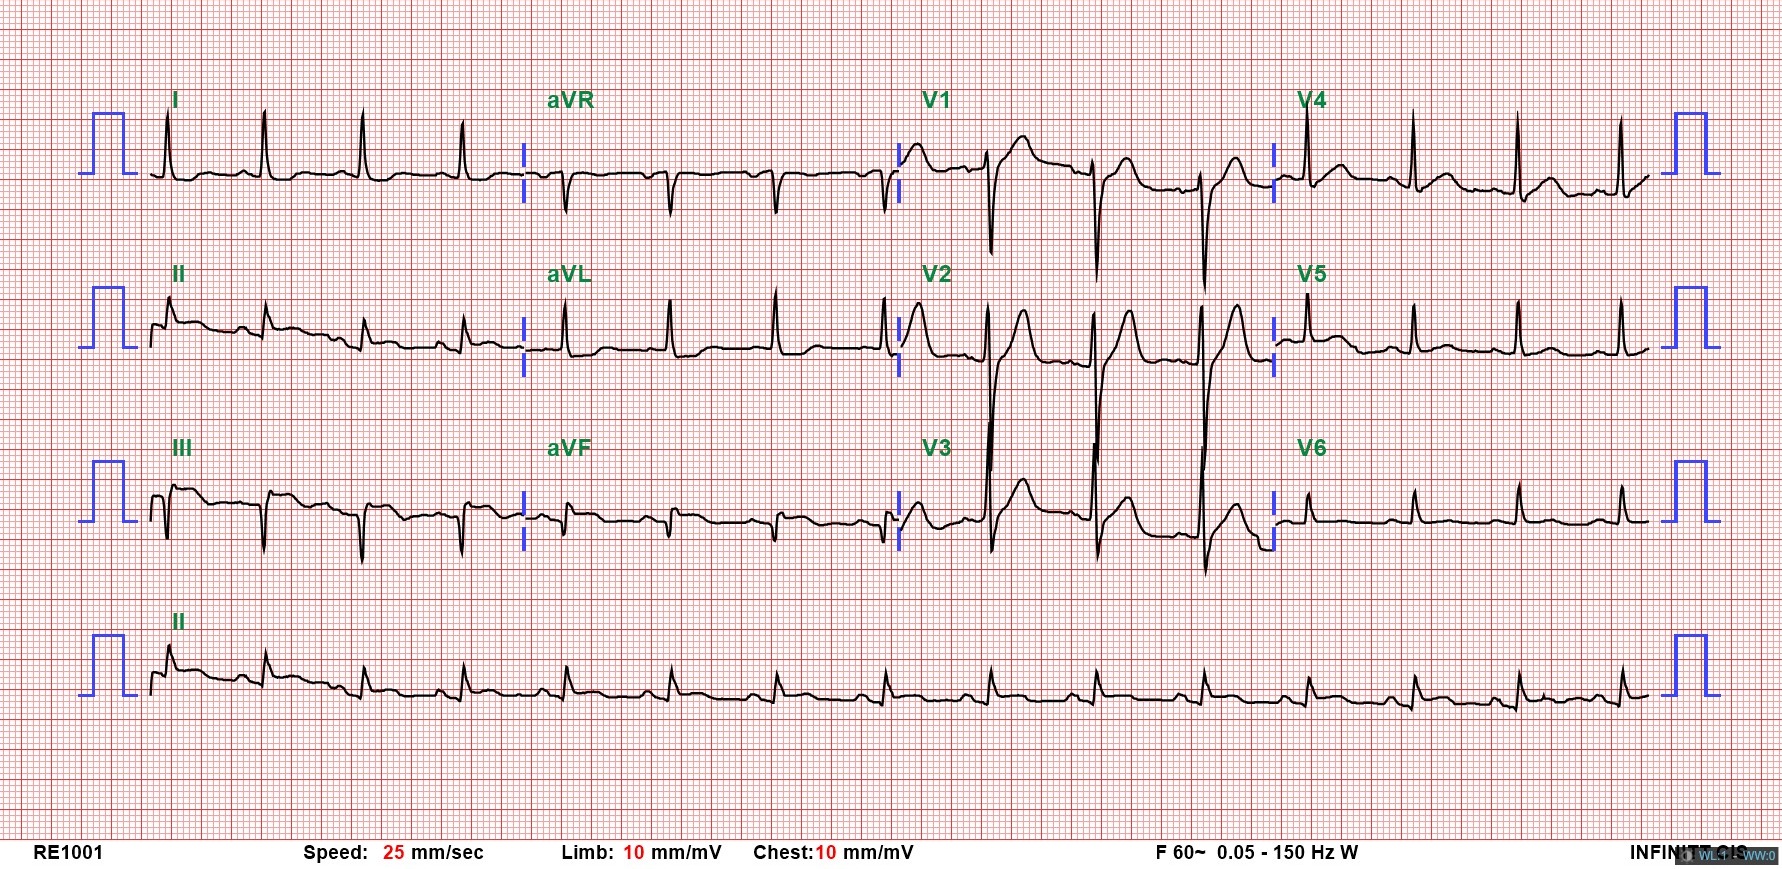

This 63-year-old male had coronary artery disease, status post angioplasty and stenting to the left anterior descending and right coronary artery (RCA). He presented to the ER with chest pain since the previous night. Examination showed stable vitals. ECG revealed sinus rhythm and Q-S pattern in leads II, III, and aVF. Elevated cardiac enzymes and echocardiography with fair ejection fraction without RWMA confirmed NSTEMI. He was admitted to the ICU, and coronary angiography planned.